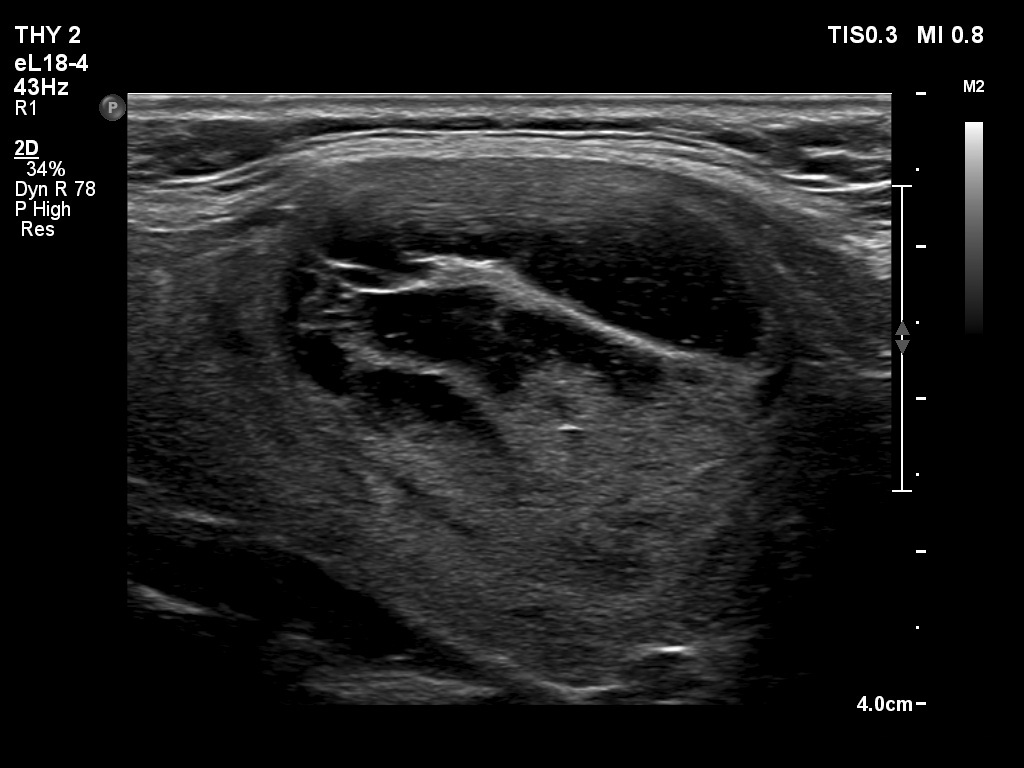

Right lobe, longitudinal scan